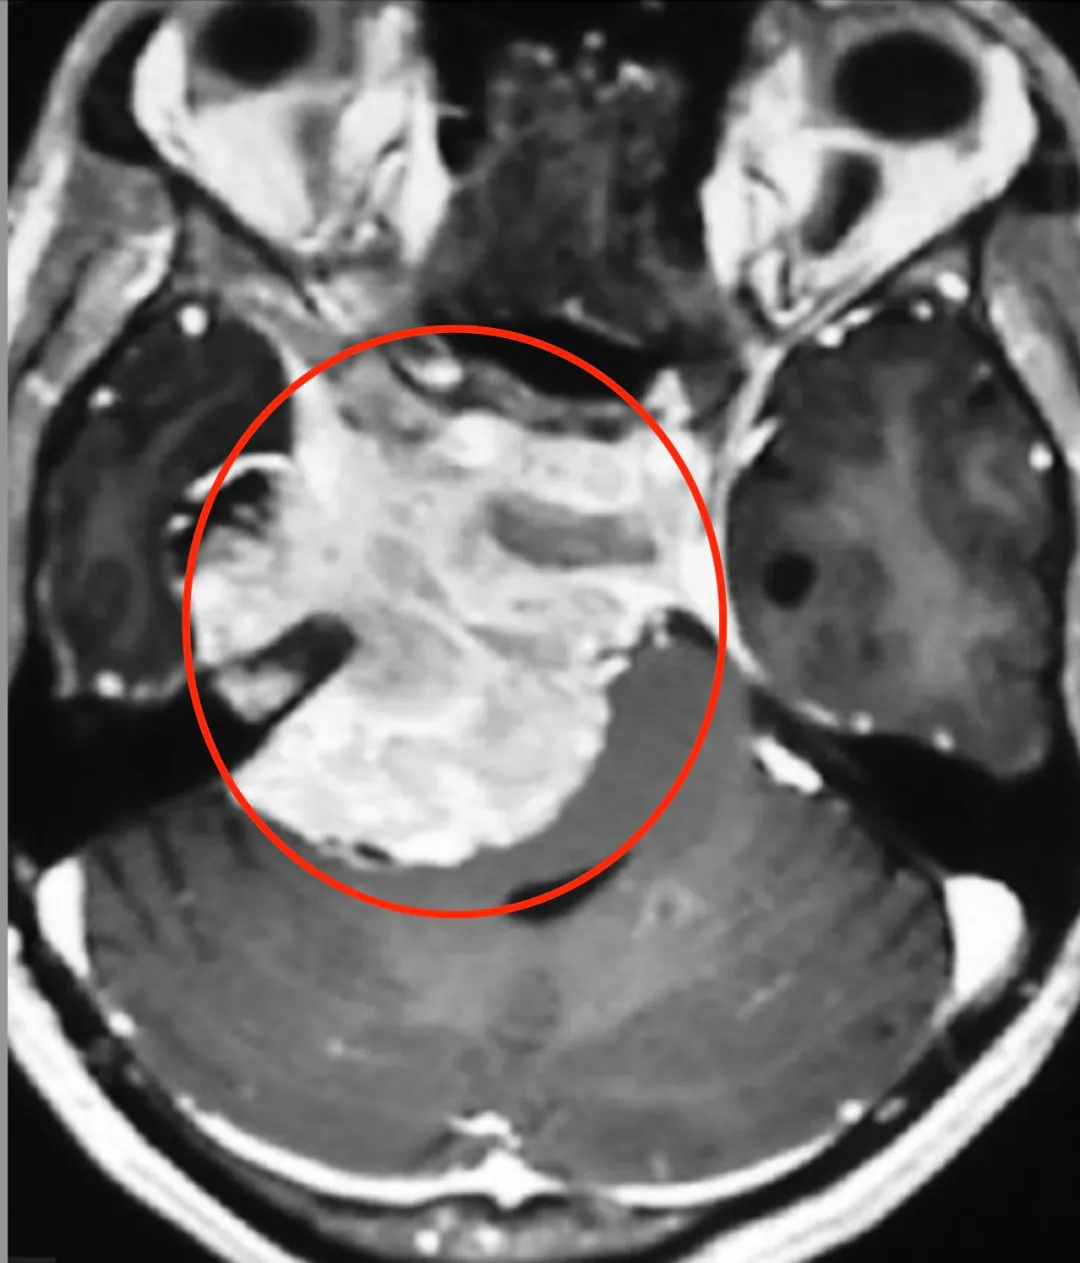

冲破CPA区,结识岩斜区的朋友们

从此我不再是小小的CPA区脑膜瘤

而是大岩斜区脑膜瘤

很多重要功能神经、脑组织、血管

见了我都要退避三舍呢

脑膜瘤沿着脑膜及自然间隙增大,继续侵犯M腔,从颅后窝跨越颅中窝并侵犯海绵窦,可进一步压迫损伤视神经、动眼神经、三叉神经等

岩斜区脑膜瘤有什么了不起呢?

岩斜区脑膜瘤是起源于以岩-斜裂为中心的中上斜坡及三叉神经内侧岩骨的脑膜瘤。因岩斜区位置隐匿,解剖结构复杂,肿瘤压迫脑干与颅底神经及血管,被认为是神经外科棘手的疾病之一。手术入路较多,术后肿瘤残留率高、患者预后差等现象目前仍然存在,术中一味地追求肿瘤全切也是导致术后高病死率、高致残率的主要因素。